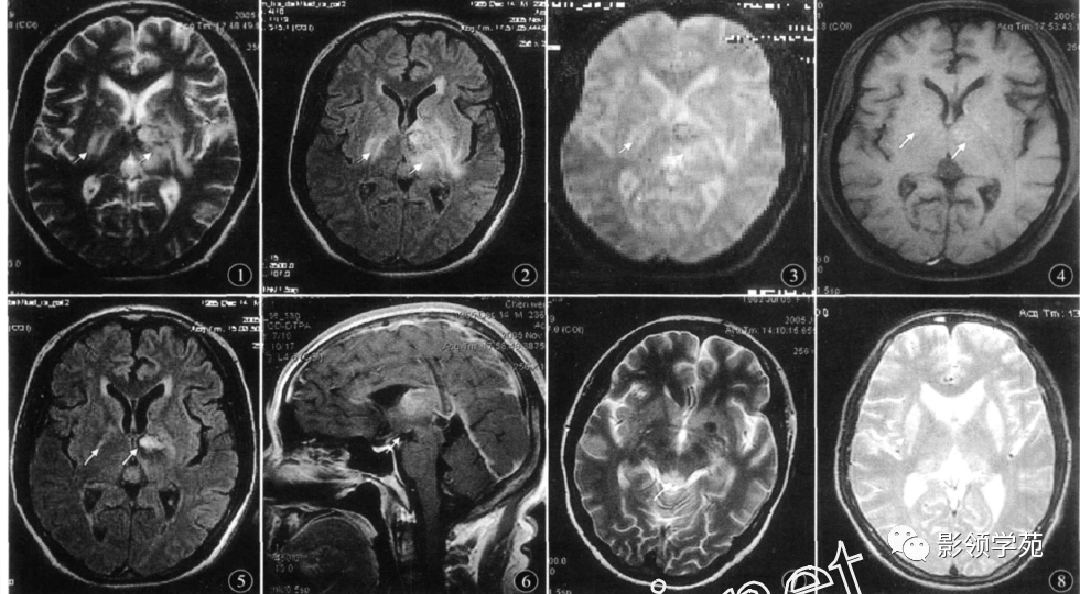

wernicke脑病mri表现

图片尺寸1080x594

wernicke脑病的影像诊断【zdzt079】

图片尺寸1080x608

wernicke脑病的影像诊断